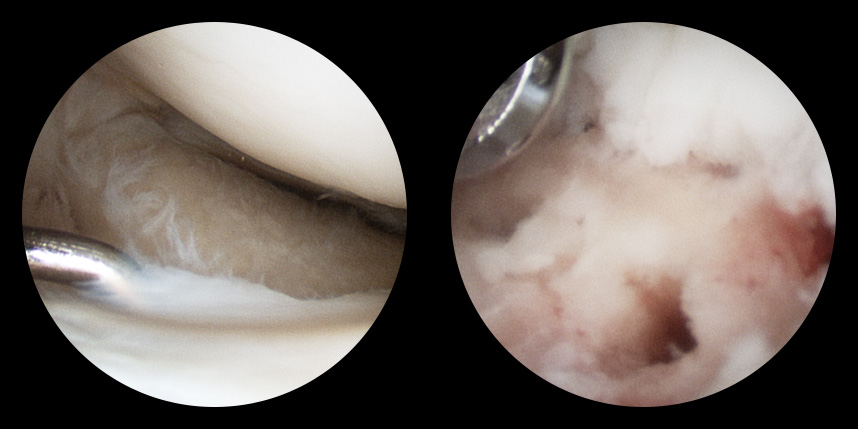

손상된 연골 부위에 작은 구멍을 뚫어 골수에서 나오는 줄기세포를 이용하여 연골 재생을 유도하는 방법으로 근본적으로 섬유연골(정상연골보다는 약한 연골)로 재생된다고 알려져 있습니다.

특수하게 농축하여 제작된 6% 콜라겐(리젠실603) 또는 9% 콜라겐(이엔카티)을 천공술을 시행한 부위에 덮어 주어 미세천공술 단독보다 좋은 치료 결과를 기대할 수 있습니다.

본원에서는 미세천공술, 콜라겐주입술, 카티스템 치료를 주로 하고 있습니다.

연골 손상이 크거나 작고 어느 위치에 있어도 연골재생술이 가능합니다.

전통적으로 증명이 된 미세천공술을 항상 같이 시행

연골재생술 진행

(미세천공술 + alpha)

타병원 미세천공술 실패 후 통증으로 내원하신 사례